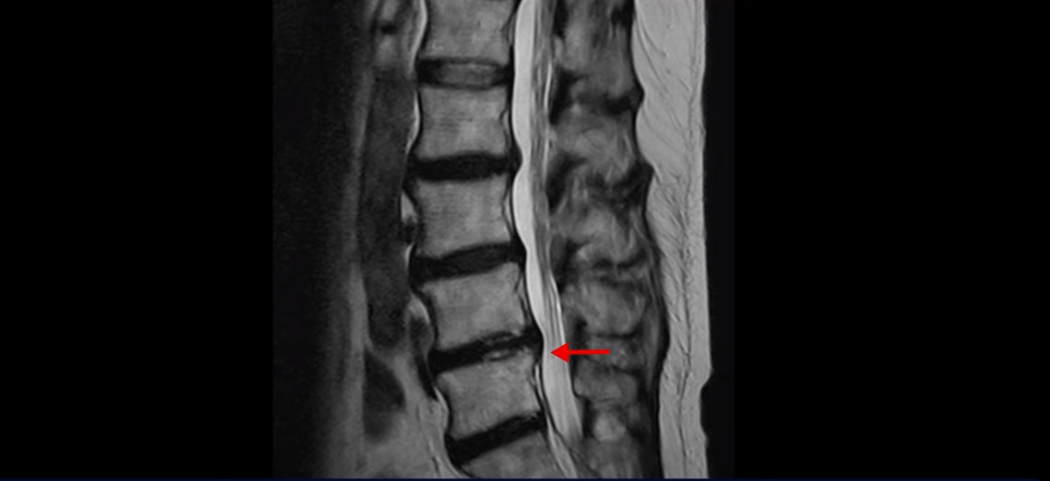

이분 MRI를 보면 여러 마디가 퇴행이 진행되어 있고

3번 4번과 4번 5번에 중심성 협착이 있는데

4번 5번이 더 심합니다.

또 4번 5번 마디에 오른쪽으로 찢어져서 밀려나온 디스크 탈출이 보입니다.

밀려나온 수핵이 조금 흘러내려 있습니다.